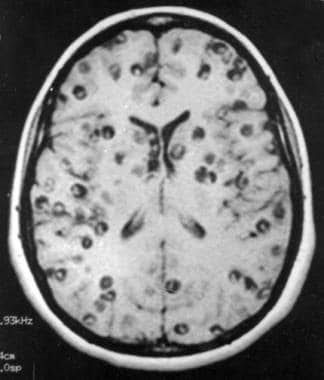

Neurocysticercosis is a preventable parasitic infection caused by larval cysts (enclosed sacs containing the immature stage of a parasite) of the pork tapeworm (Taenia solium). The larval cysts can infect various parts of the body causing a condition known as cysticercosis.